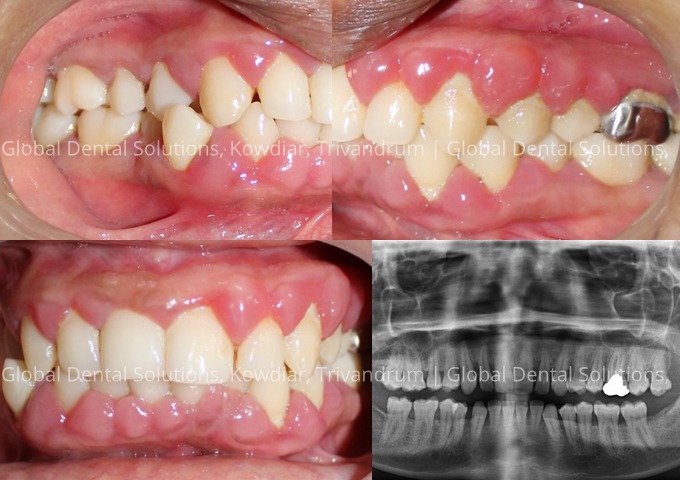

Surgical Management of Gum Disease - Flap Surgery